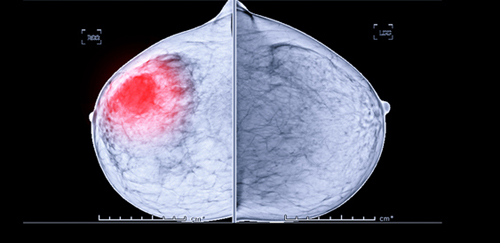

유방암 검진은 기계를 이용해 엑스레이 사진을 찍는 방식이 있고, 초음파로 하는 방식이 있습니다. 검진을 해보신 분들은 알겠지만, 엑스레이 사진을 찍을 때는 기계로 가슴을 눌러 찍기 때문에 통증은 물론이고, 굉장히 민망하기도 합니다. 여자들 사이에서는 굴욕과 통증으로 유명한 검진이기도 하지요. 하지만 검진을 소홀히 할 수는 없을 텐데요. 이번에는 유방암 원인과 유방암 초기증상을 한 번 살펴보도록 할게요.